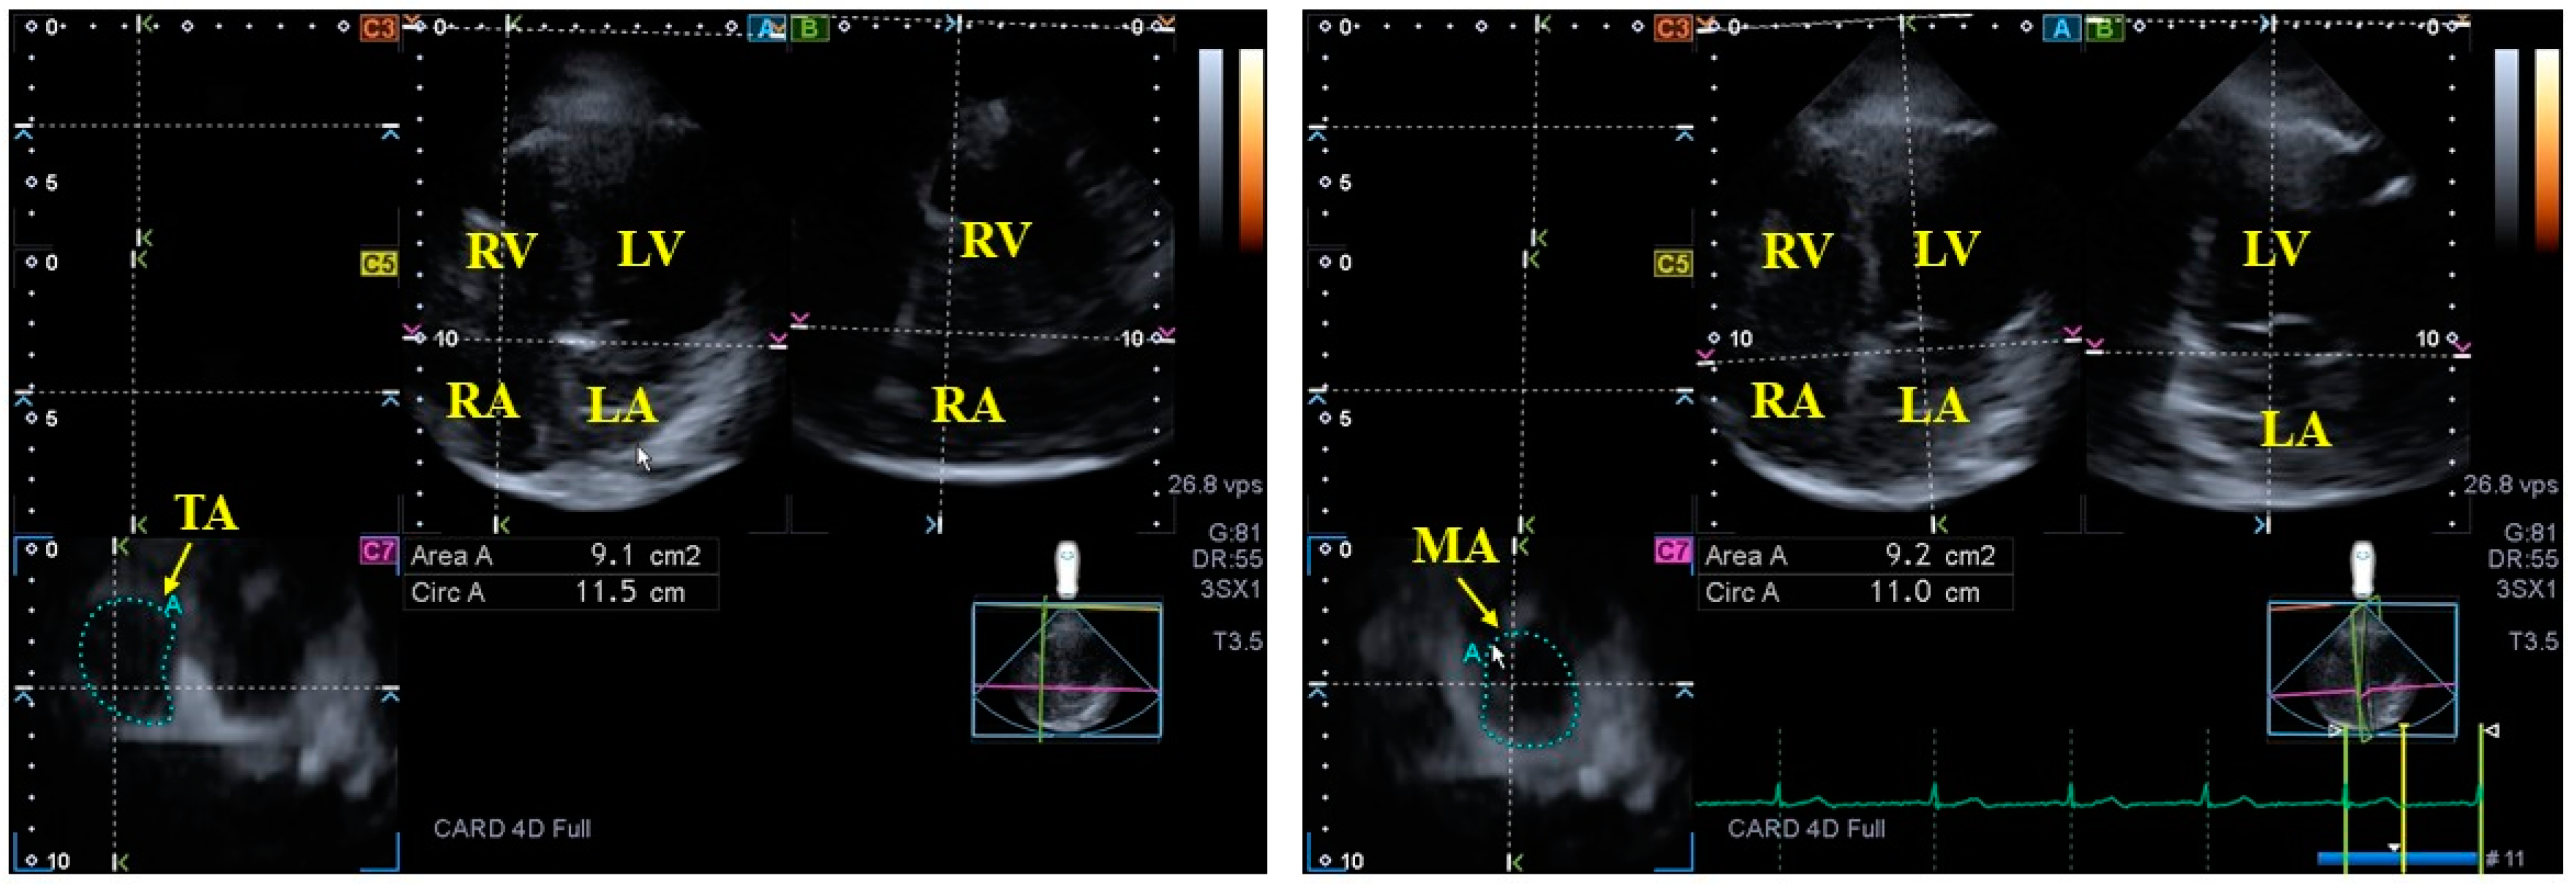

- Nemes, A.; Földeák, D.; Kormányos, Á.; Domsik, P.; Kalapos, A.; Borbényi, Z.; Forster, T. Cardiac Amyloidosis Associated with Enlargement and Functional Impairment of the Mitral Annulus: Insights from the Three-Dimensional Speckle Tracking Echocardiographic MAGYAR-Path Study. J. Heart Valve Dis. 2017, 26, 304–308. [Google Scholar] [PubMed]

- Nemes, A.; Rácz, G.; Kormányos, Á.; Földeák, D.; Borbényi, Z. The tricuspid annulus in amyloidosis with cardiac involvement: Detailed analysis from the three-dimensional speckle tracking echocardiographic MAGYAR-Path Study. Int. J. Cardiol. Heart Vasc. 2022, 40, 101026. [Google Scholar] [CrossRef]